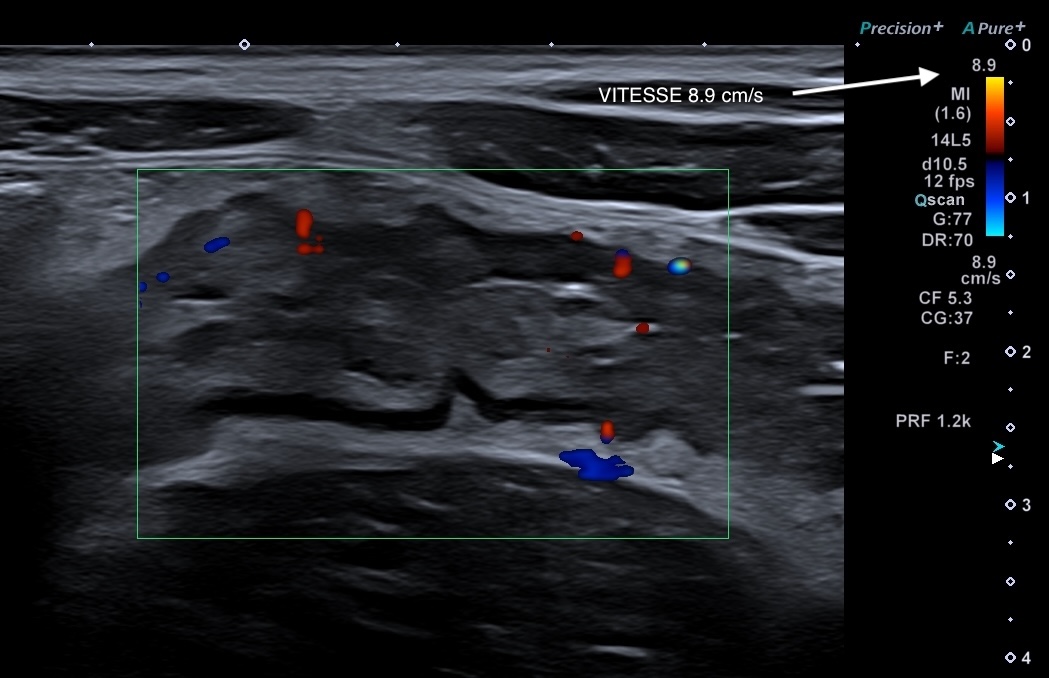

Doppler classique Limberg 1 sur l'image (limité à la paroi et faible) Crohn jéjunal

La couleur représente le sens du flux

(rouge vient vers la sonde, bleu s'éloigne, peu utile en microcirculation)

La taille de la fenêtre est adaptée à la paroi étudiée